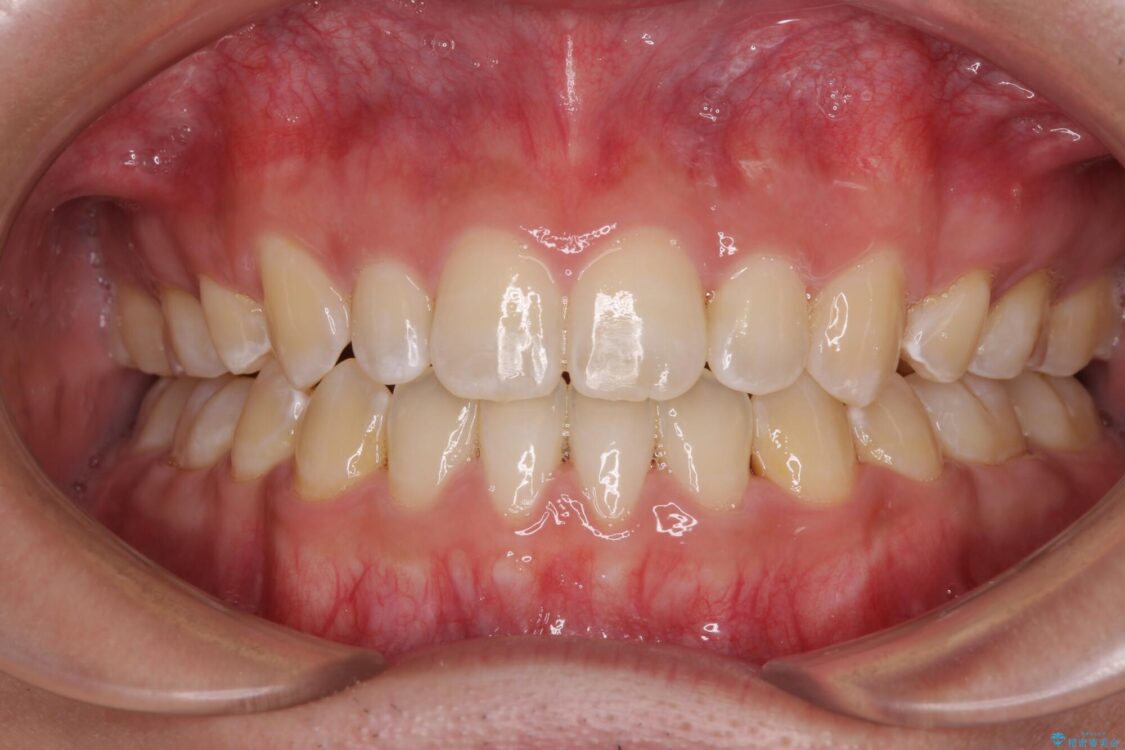

受け口傾向の咬み合わせと口元の突出感を気にして来院された患者様です。

治療前

• 口元の突出感を改善 受け口傾向の咬み合わせの抜歯矯正 治療前画像